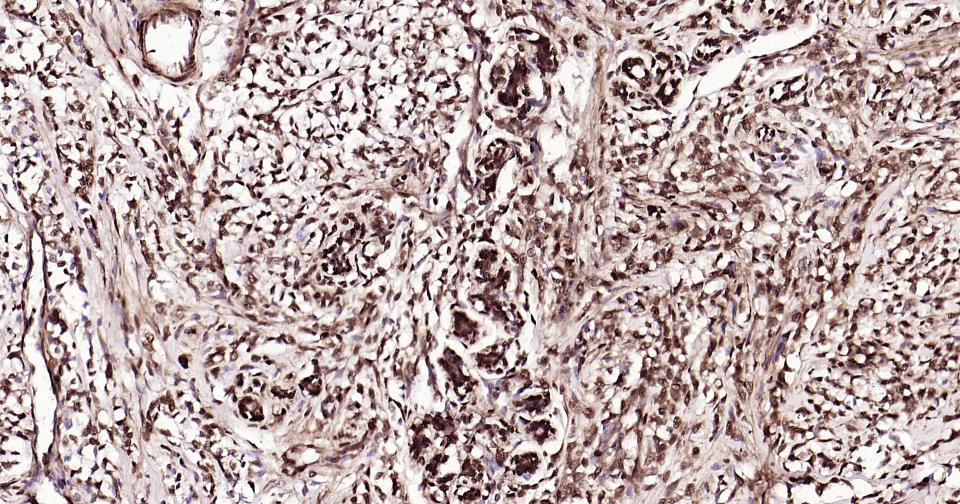

Paraformaldehyde-fixed, paraffin embedded Human Breast Cancer; Antigen retrieval by boiling in sodium citrate buffer (pH6.0) for 15 min; Antibody incubation with K27-linkage specific ubiquitin Monoclonal Antibody, Unconjugated(bsm-63007R) at 1:200 overnight at 4°C, followed by conjugation to the bs-0295G-HRP and DAB (C-0010) staining and DAB (C-0010) staining.